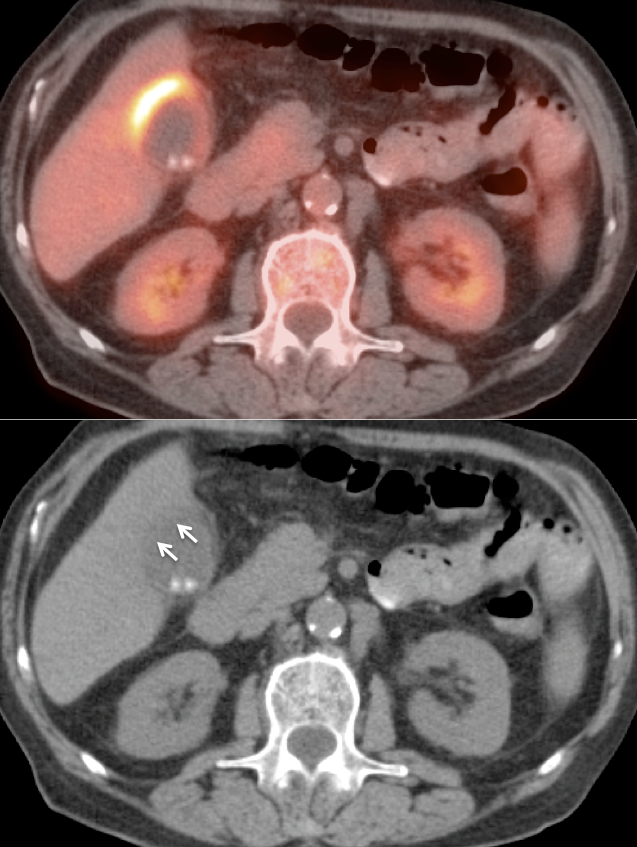

- The Heterogeneous Liver

- Liver Ablation

- Hypermetabolic Geographic Fatty Infiltration